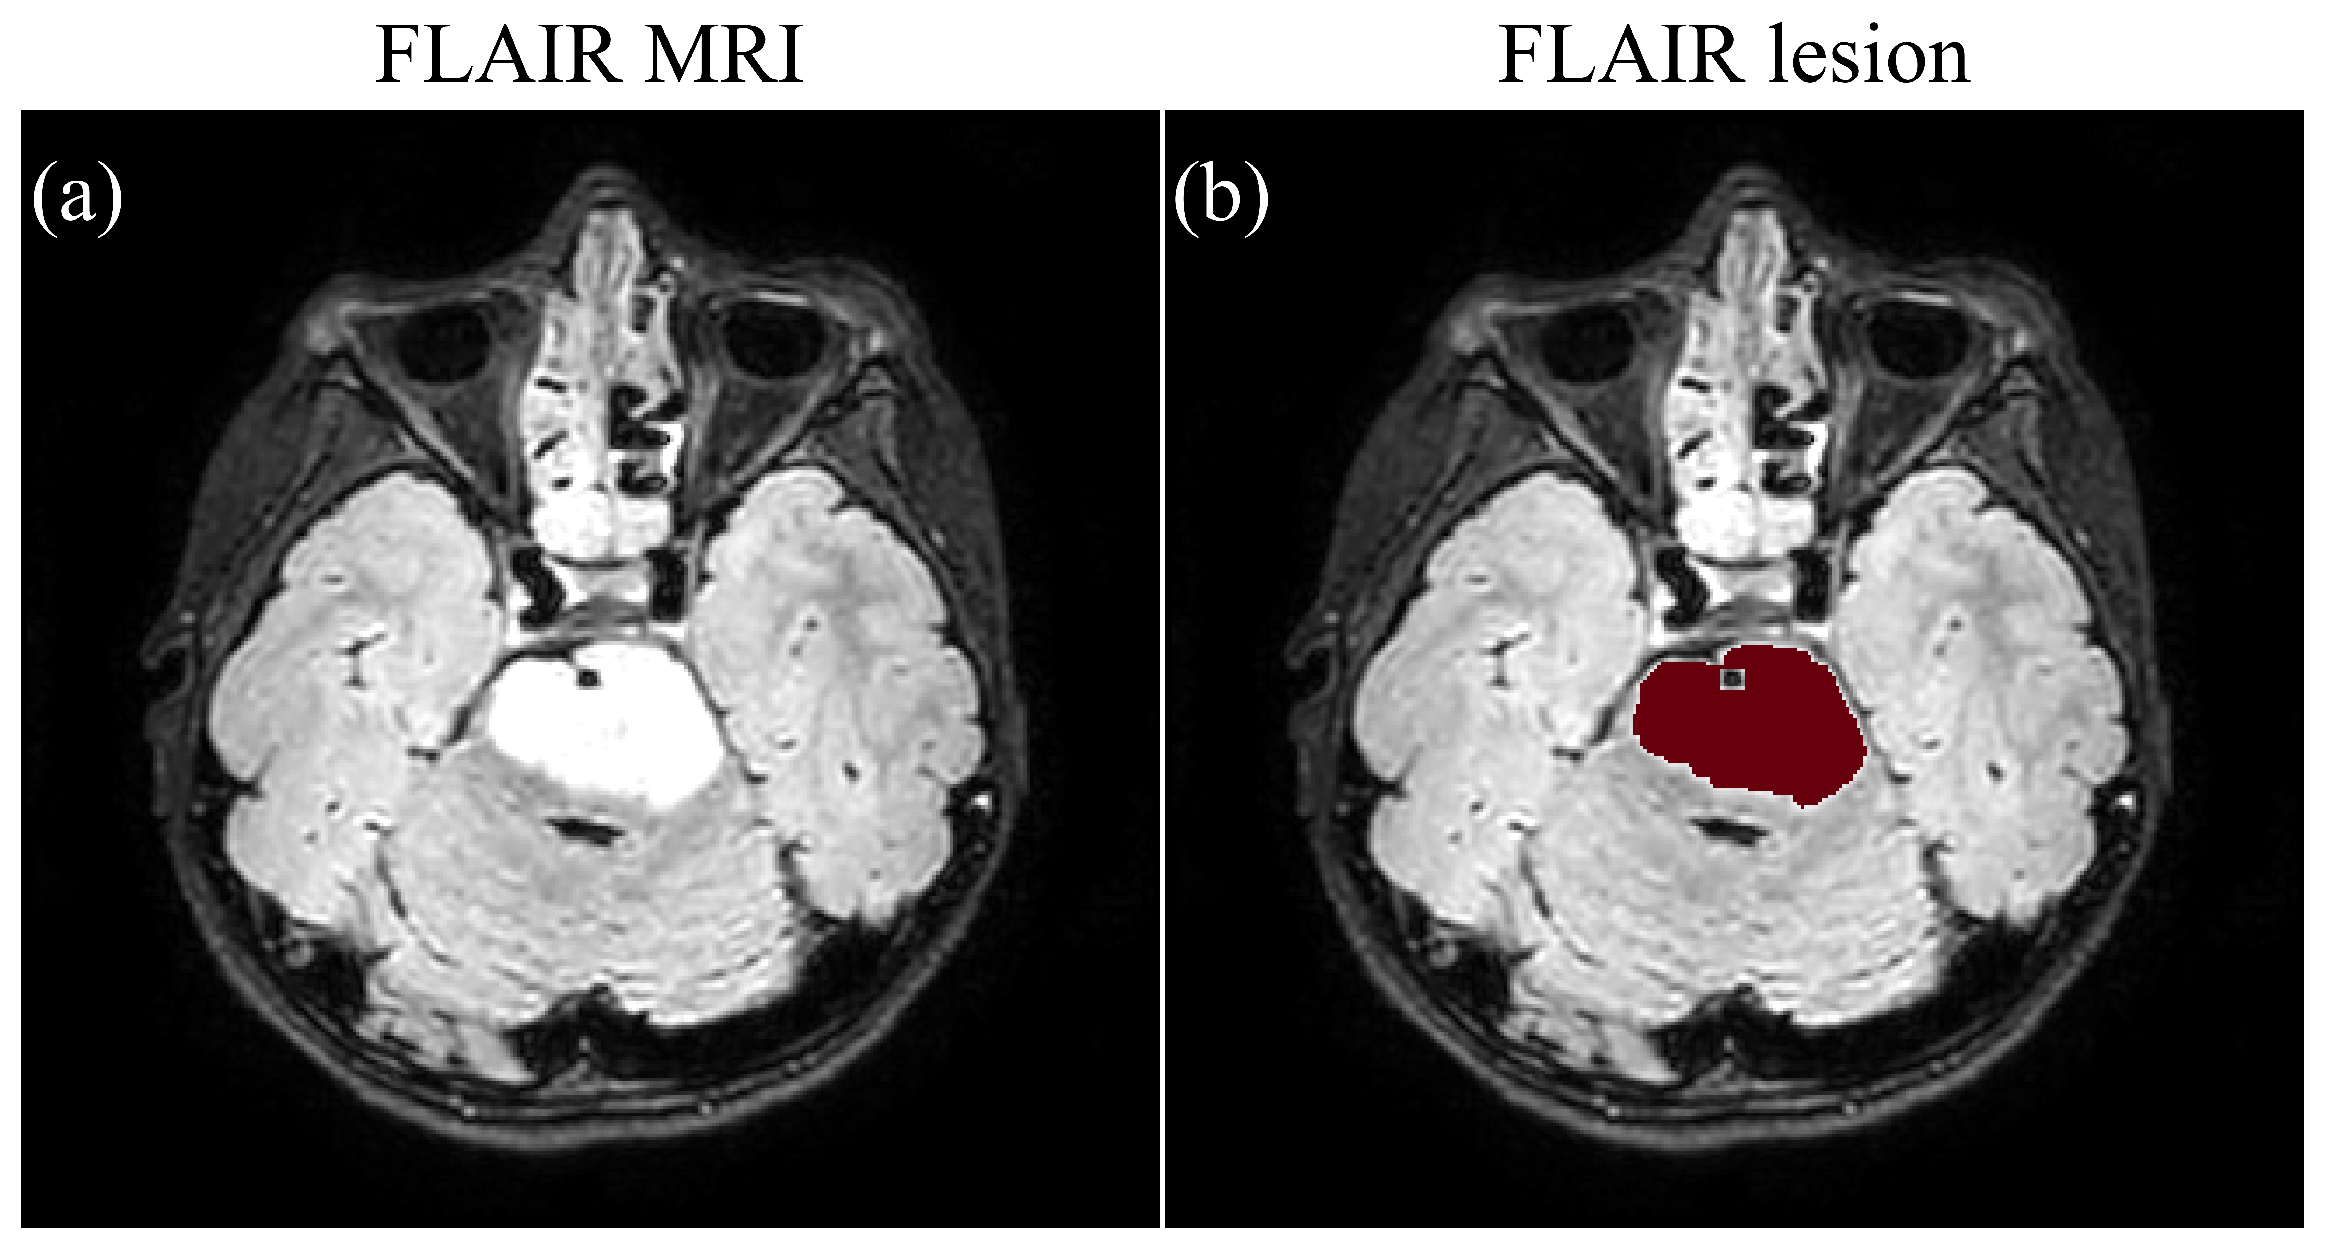

2.4.1. FLAIR MRI Segmentation

- Next, the tumor mask was refined by removing small connected components and integrating it with the FLAIR tumor using logical OR operation. A Gaussian filter, with FWHM equal to 5, was applied to generate a probability distance map.